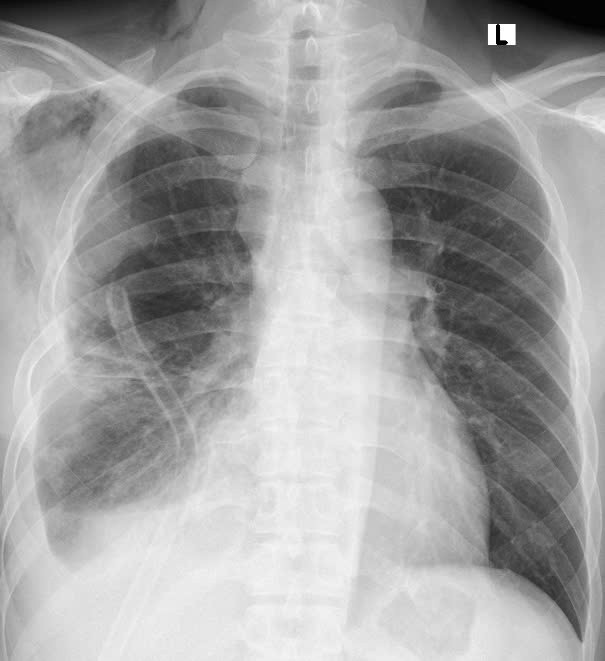

u-trung-that-kl.jpg

Khối u trung thất khổng lồ trên phim chụp - Ảnh BVCC

Bệnh nhân Nguyễn V T (36 tuổi, ở TP Hạ Long, tỉnh Quảng Ninh) không có triệu chứng đau ngực, khó thở chỉ tức nặng ngực khi vận động. Khám sức khỏe tại Bệnh viện Bãi Cháy, kết quả chụp CTscanner lồng ngực của bệnh nhân phát hiện khối u có cấu trúc hỗn hợp gồm mô đặc, mỡ, vôi hóa, kích thước 12,3cm x 18,3cm x 25,2cm nằm ở trung thất trước bên phải, đè ép vào nhu mô phổi phải, tĩnh mạch chủ trên.

Phẫu thuật viên đã tạo đường vào từ khoang liên sườn phải, tiếp cận khối u. Quan sát thấy khối u trung thất kích thước lớn 20cm x 25 cm kéo dài từ đỉnh phổi xuống bờ sườn, mật độ chắc, dính vào mặt trung thất, 1 phần dính nhu mô phổi nhiều mạch máu nuôi xuất phát từ trung thất.